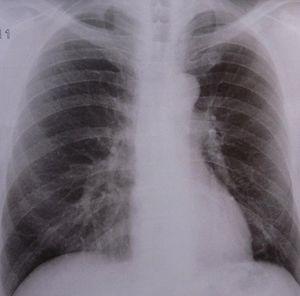

Lunge: COPD nimmt vielen Menschen den Atem (Foto: pixelio.de, Dieter Schütz) |